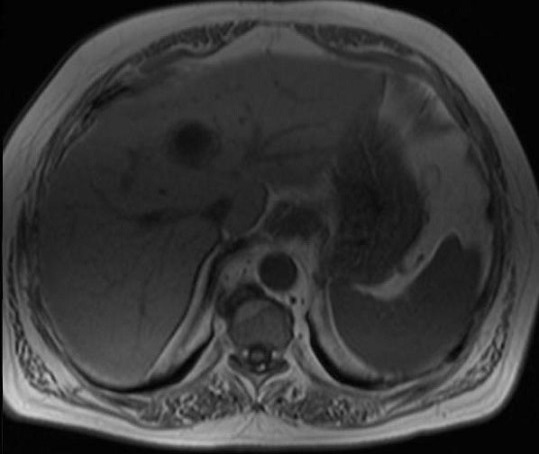

Image

radiologique IRM de abces du foie : Character

de signal est :

| |

-Image ponderee en T1 : le plus souvent

est hyposignal au centre et heterogene ..

Hyperintense dans abces fungale |

-Image ponderee en T2 : Aspect

hypersignal lesionnel . |

Image IRM ponderation

T1 d'une kyste hydatique du foie : Aspect

radiologique est une formation lesionaire arrondie

hyposignal avec paroi legere epaissisement

hypersignal |